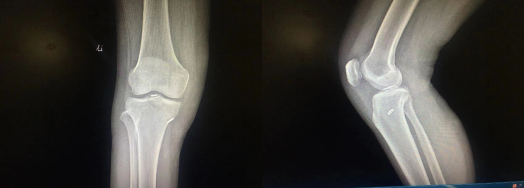

患者,女,35岁,“因右膝外伤肿痛1天”入院。CT示:右胫骨平台髁间骨折,MR检查提示:右膝关节内侧副韧带损伤。完善术前准备后,行“关节镜下右膝髁间棘骨折内固定术+内侧副韧带修复术”,术后恢复良好。

膝关节交叉韧带止点撕脱骨折

膝关节交叉韧带止点撕脱骨折,好发于青壮年,男性患者多于女性。属于关节内骨折,损伤处多位于交叉韧带止点,容易引起膝关节功能障碍。传统的切开复位内固定手术,创伤较大,容易引起关节粘连。骨块较小或者很薄的时候,固定困难,容易引起骨折块的再骨折。关节镜下固定手术方式创伤小,对于小的撕脱骨折块可以结合高强线镜下缝合捆绑固定,可实现骨折块解剖复位和牢固内固定,满足早期锻炼需要,减少术后关节粘连等并发症,不需要二次手术拆除内固定。但该手术需要丰富的关节镜手术经验,学习周期长。随着关节镜技术的普及,该项手术已逐渐成为交叉韧带止点撕脱骨折主流手术方式。